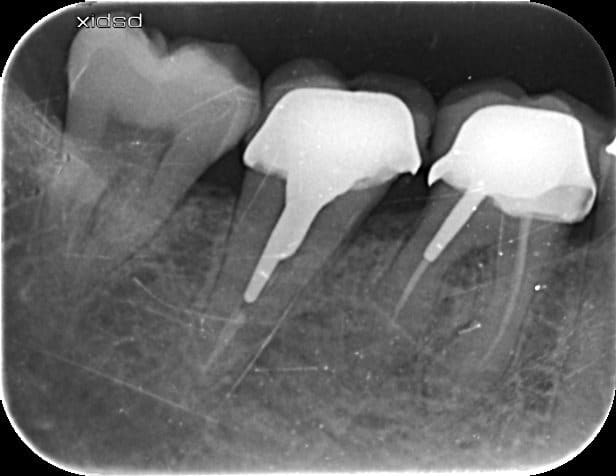

Bonjour j'ai posé cette couronne et fait le traitement endo de 47 il y a 2 mois

depuis le patient a mal a la percussion...

Anatomie atypique, j'avais 2 canaux se rejoignant à l'apex.

Je ne comprends pas d'ou peut provenir cette douleur...

Arthrite? léger débordement ccm en m de 47? contrôle point de contact avec 46

Fracture racine ?

3eme canal ??????

j'ai rien vu, rien a signaler lors de l'endo a part l'anatomie atypique de la dent (2 canaux se rejoignant à l'apex)

est ce qu'un cone beam pourrait m'aider à y comprendre quelquechose?

ENdo fait le 12/11/15

Pose inlay core + prov le 17/12/15

pose de la ccm le 04/02/16

il a mal depuis la pose de la ccm. Fichtre!